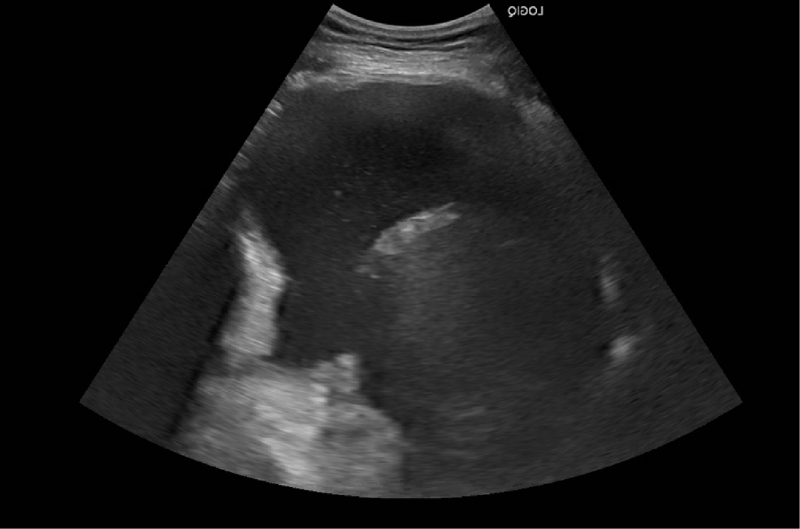

A pulmonary specialist performed an ultrasound-guided thoracentesis and removed 1.7 liters of milky fluid (Figure 3). Pleural fluid analysis revealed triglycerides of 5,136 mg/dL (Table 1). The patient was monitored for two days in the hospital with serial chest x-rays and bedside ultrasound to evaluate for fluid accumulation, and she remained asymptomatic without recurrence of the pleural effusions. The patient was discharged home with instructions to eat a high-protein, low-fat (<10 g fat/day) diet to minimize the flow of chyle through the thoracic duct, because decreasing fat intake decreases fat absorption from the gut and therefore the flow of chyle. The patient was educated about the expected progression of the problem, the schedule for monitoring, and dietary modification. Other diagnostic and therapeutic options like a lymphangiogram or pleurodesis would be considered if the conservative management failed and the chylothorax recurred.3,4

Figure 3

Figure 3. Ultrasound of the right chest revealing a large right-sided pleural effusion.